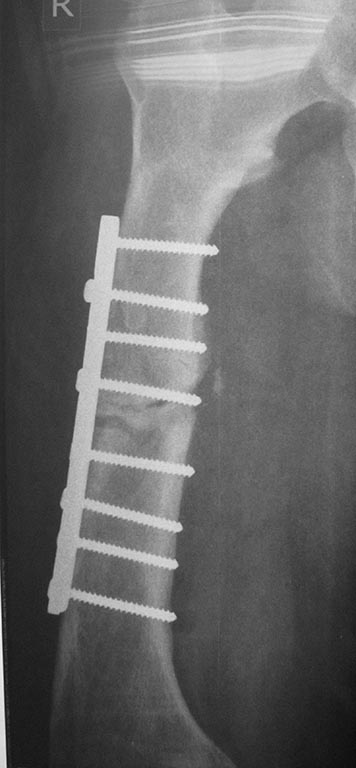

Re: перелом бедра с исходной деформацией

Выкладываю, как и обещал. За репозицию педплечья не осуждайте!